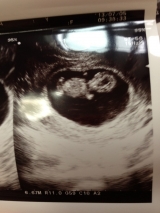

10w5d

昨日は3ヶ月最後の検診。

尿検査で、ケトン体が+4のMAX。ツワリがキツイとは思ってたけど、そんなとは…。自分でもビックリ。

点滴1本、3時間打って少し楽になりました。でも効き目は1、2日みたい。

赤ちゃんは元気に動いてました!

よかったよ~。

病院代 診察+血液検査+点滴 22000円

補助使っても結構したな…。